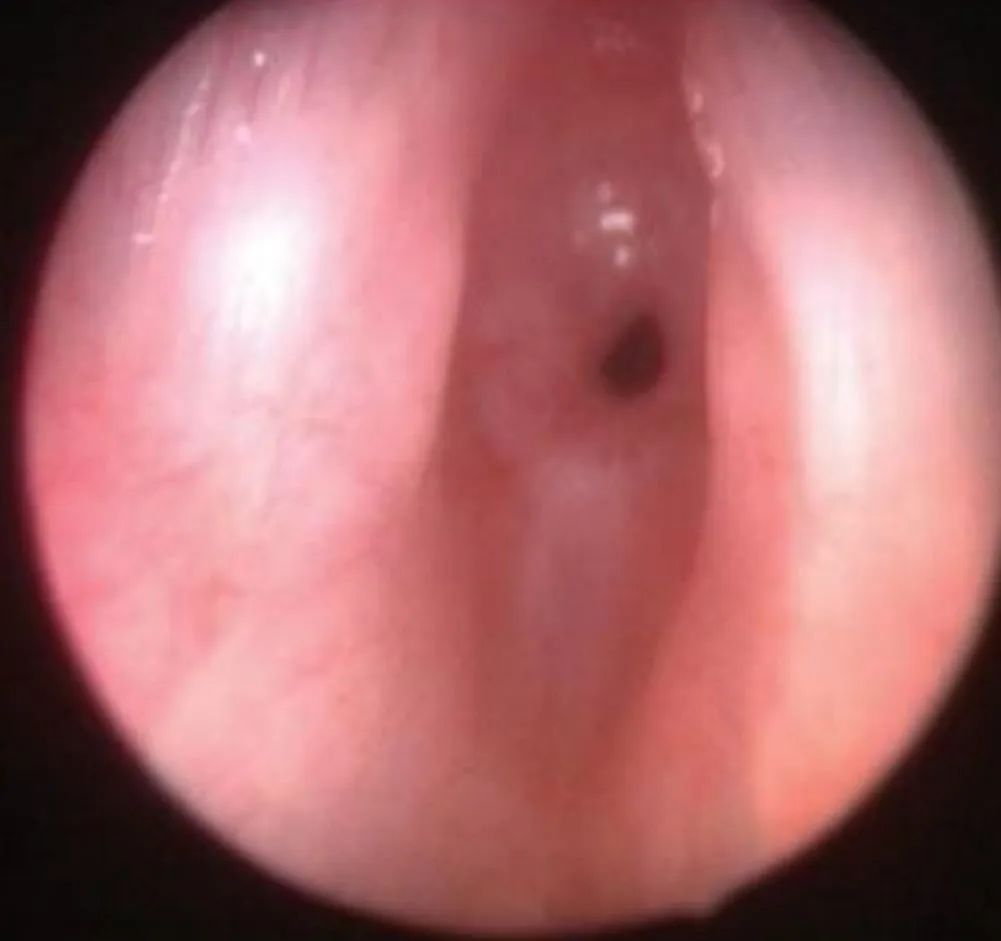

喉镜视图:中间那个小孔就是气道开口,图源:凌楚眠医生

最恐怖的情况:视野里灰茫茫一片,真正的气道开口就光圈那么小点…